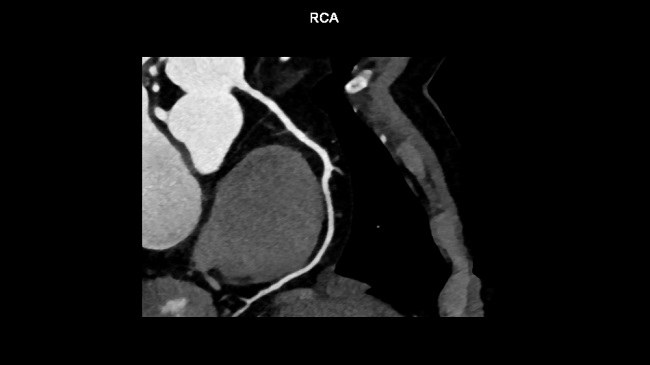

Sejak publikasi pertama mengenai rekomendasi pelaksanaan CCTA pada tahun 2009, perkembangan tekhnologi multi-detector row computed tomography (MDCT) meningkat pesat, terutama dalam hal kemampuan akuisisi gambaran jantung dan arteri koroner secara noninvasif, sehingga dapat mendukung identifikasi stenosis arteri koroner. [2] Beberapa meta analisis dan studi klinis acak terkontrol telah melaporkan akurasi diagnostik CCTA dengan 64-slice CT, berupa sensitivitas berkisar 93-97% dan spesifisitas 80-90% dalam mendeteksi obstruksi arteri koroner dibandingkan dengan angiografi koroner invasif.[1]

Dalam uji klinis CORE-320 (Combined Non-invasive Coronary Angiography and Myocardial Perfusion Imaging Using 320 Detector Computed Tomography) yang melibatkan 391 subjek, didapatkan bahwa CCTA memiliki sensitivitas yang lebih baik dibandingkan single-photon emission computed tomography (SPECT) myocardial perfusion imaging dalam mendeteksi pasien dengan stenosis ≥50% pada angiografi koroner invasif (0,92 vs 0,62).[5]

Studi EVINCI (Evaluation of Integrated Cardiac Imaging in Ischemic Heart Disease) juga mendapat hasil serupa. Studi ini menyebutkan bahwa CCTA memiliki sensitivitas 91% dan spesifisitas 92% dibandingkan SPECT myocardial perfusion imaging (sensitivitas 74% dan spesifisitas 73%) dalam mendeteksi penyakit arteri koroner signifikan.[6]

Meta analisis COME–CCT (Collaborative Meta-Analysis of Cardiac CT) oleh Haase et al, mencoba menilai apakah CCTA perlu dilakukan pada semua pasien yang diduga mengalami penyakit jantung koroner dan apakah performa diagnosis berbeda pada berbagai subgrup. Meta analisis ini mengikutkan 65 studi prospektif dengan jumlah total subjek 5.332 pasien. Hasil studi menunjukkan bahwa CCTA memiliki rerata sensitivitas sebesar 95,2% dan spesifisitas 79,2%. Performa CCTA dilaporkan tidak dipengaruhi oleh jenis dari angina pektoris, performa sedikit lebih tinggi pada pasien berjenis kelamin laki-laki, serta sedikit lebih rendah pada pasien usia tua.[7]